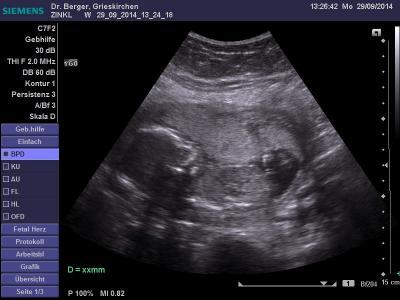

Hatte gestern meine 3. Mutterpass-Untersuchung in Wo. 17+6

Mein Arzt gab sich auch viel Mühe das Geschlecht erkennen zu können, sagte aber schließlich, dass er es nicht sicher sagen könne und wir nächstes Mal vielleicht mehr Glück hätten. Er fragte mich was ich mir wünschen würde und ich meinte, dass es mir völlig gleich wäre da ich ja bereits ein Pärchen habe, aber mein Sohn sich unbedingt einen Bruder wünscht. Darauf meinte er, etwas gesehen zu haben, das darauf hindeuten würde, dass es MÖGLICHERWEISE tatsächlich ein Junge werden würde.

Schick auch mal wieder ein Bildchen mit :)

Sorry, ich würde da sagen es ist nicht eindeutig. Das kann auch die Nabelschnur sein. Ich würde nicht eindeutig einen Jungen sehen. Von unten wäre besser